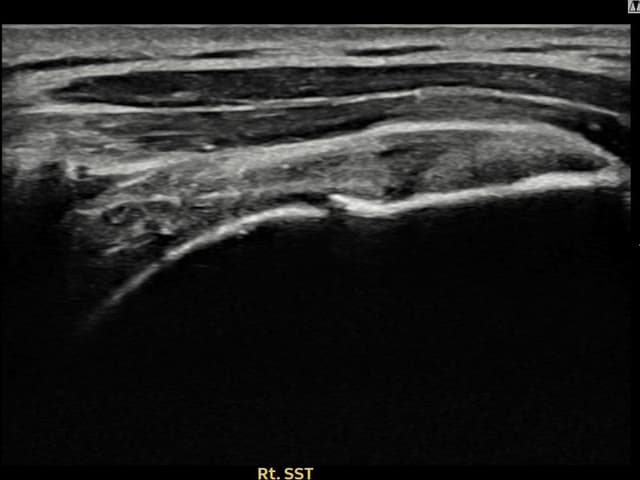

[経過期間: 22.08.10]

[石灰破砕吸引術] X線で右肩棘上筋腱内の石灰沈着(14mm × 10mm)を確認し、超音波ガイド下石灰破砕吸引術を施行しました。6本分の石灰を吸引し、術後4日後の追跡X線で石灰陰影の著明な減少を確認しました。